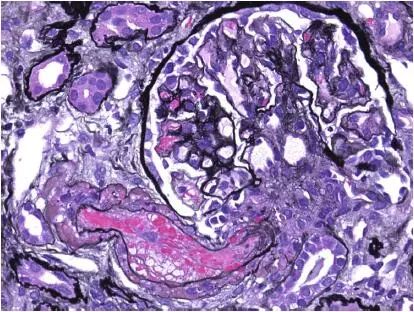

图2 CNI肾毒性TMA,肾小球毛细血管袢和血管极(Jones 银染)

CNI肾毒性导致的血管收缩无形态学变化。急性CNI肾毒性特征包括:近端肾小管上皮细胞空泡化,大小一致;血管损伤,平滑肌细胞丢失;肌细胞胞浆空泡化;细胞坏死或凋亡退化。肌细胞损伤最终发展为局灶性结节性玻璃样变和透明样变,可延伸至小动脉和动脉血管壁整个中层。CNI肾毒性还可引起血栓性微血管病变(TMA),主要累及小动脉和肾小球毛细血管袢。慢性CNI毒性特征为:条状间质纤维化,肾小管萎缩。

近端肾小管上皮细胞空泡化,大小相等,内质网扩张,大型溶酶体。动脉中层和外膜透明质酸积聚。TMA患者可出现肾小球内皮细胞肿胀,内层扩张和肾小球系膜溶解。